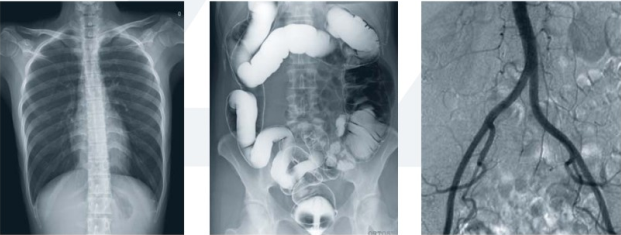

數字平板胃腸機屬于多功能X線機,除具有傳統胃腸機所有功能外,還有DR平板探測器X線攝影所有功能,主要用于消化道對比造影、消化道吞咽造影、全脊柱拼接攝影、全下肢拼接攝影、ERCP、泌尿系造影、“T”管造影、鋇劑灌腸、四肢造影、子宮輸卵管造影等各類檢查,是檢查消化道潰瘍、腫瘤、異物等疾病的主要方法之一。

數字平板胃腸機不僅可以做普通的胃、食管鋇餐透視,胸腹部的常規透視檢查,而且圖像更清晰,多了數字化處理過程,還可以實時點片,更便捷的獲得實時圖像,及時抓拍住病灶圖像,為患者留存影像資料。這就像我們的手機抓拍瞬間圖像保存到手機相冊一樣,能夠診斷早期食道癌、胃癌、小潰瘍等疾病。

平板胃腸機臨床影像